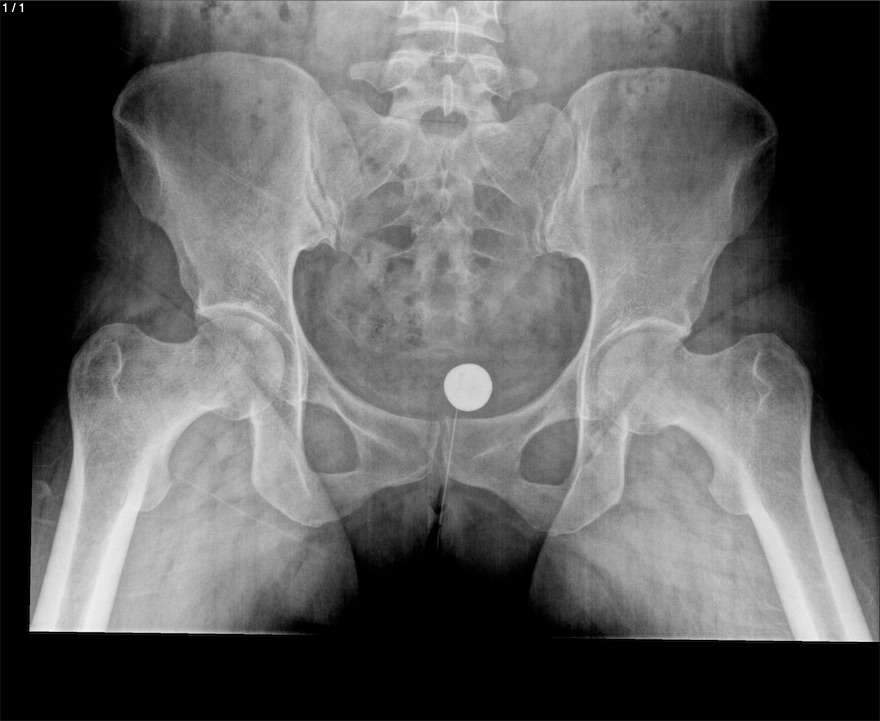

Blanca Flor Alvarez Marroquin - Unnamed